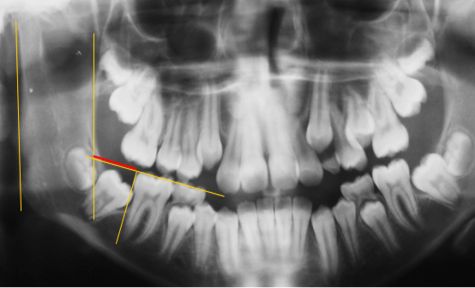

A cross-sectional study was conducted using non-probability, consecutive sampling from a universe of 4,500 records of initial consultations in two private clinics in the city of Temuco, Chile. The records of 2095 individuals of both sexes were analyzed. Criteria for inclusion: clinical records with printed panoramic radiographies taken between 2008 and 2013 to children aged between 7 and 13, with at least one second permanent molar with mesial contact point located under the amelocemental junction of the first permanent molar. Criteria for exclusion: presence of syndromic pathology and second permanent molar absent or divergent (distal coronal inclination). The sample was formed by 370 clinical records that fulfilled the criteria for inclusion. Finally, 740 permanent lower second molars were analyzed. The variables measured were angle of second molar (Fig.1), angle of first and second permanent lower molars in relation to occlusal plane (Fig. 2), invasion of distal space of first molar by second molar (Fig. 3), distance between distal edge of first molar and front edge of ramus (Fig. 4).

To determine the angles with regard to the occlusal plane, the central lines of the axis of the molars and a line drawn on the occlusal plane on the right side and another on the left side were used (Fig. 2). To determine distal invasion of the first molar, a line parallel to the axis of the first molar was drawn. The line went through the most distal point of the crown. Then, the area of the second molar within this space was measured in millimeters (Fig. 3). To determine distal space of the first molar, the most distal point of the crown of the first molar was determined and a line parallel to the axis of the first molar was drawn. Then a line on the front edge of the ramus was drawn, and the line of the occlusal plane was extended distally. Finally, measurements were taken in mm following the occlusal line (Fig. 4). An Excel spreadsheet was used to record the data, and a manual direct method was used to measure the elements on the panoramic radiographies. The instruments used to take the measurements were acetate sheets (cephalometric analysis) and lead pencil, and to measure the angles a goniometer (BaselineTM CE Diagnostic and Measuring Instruments) was used. Descriptive statistics were applied using SPSS 15.0.1 for Windows (LEAD Technologies, Inc. 2006).

Fig. 2. Inclination of 1st and 2nd molars in relation to occlusal plane and front edge of ramus